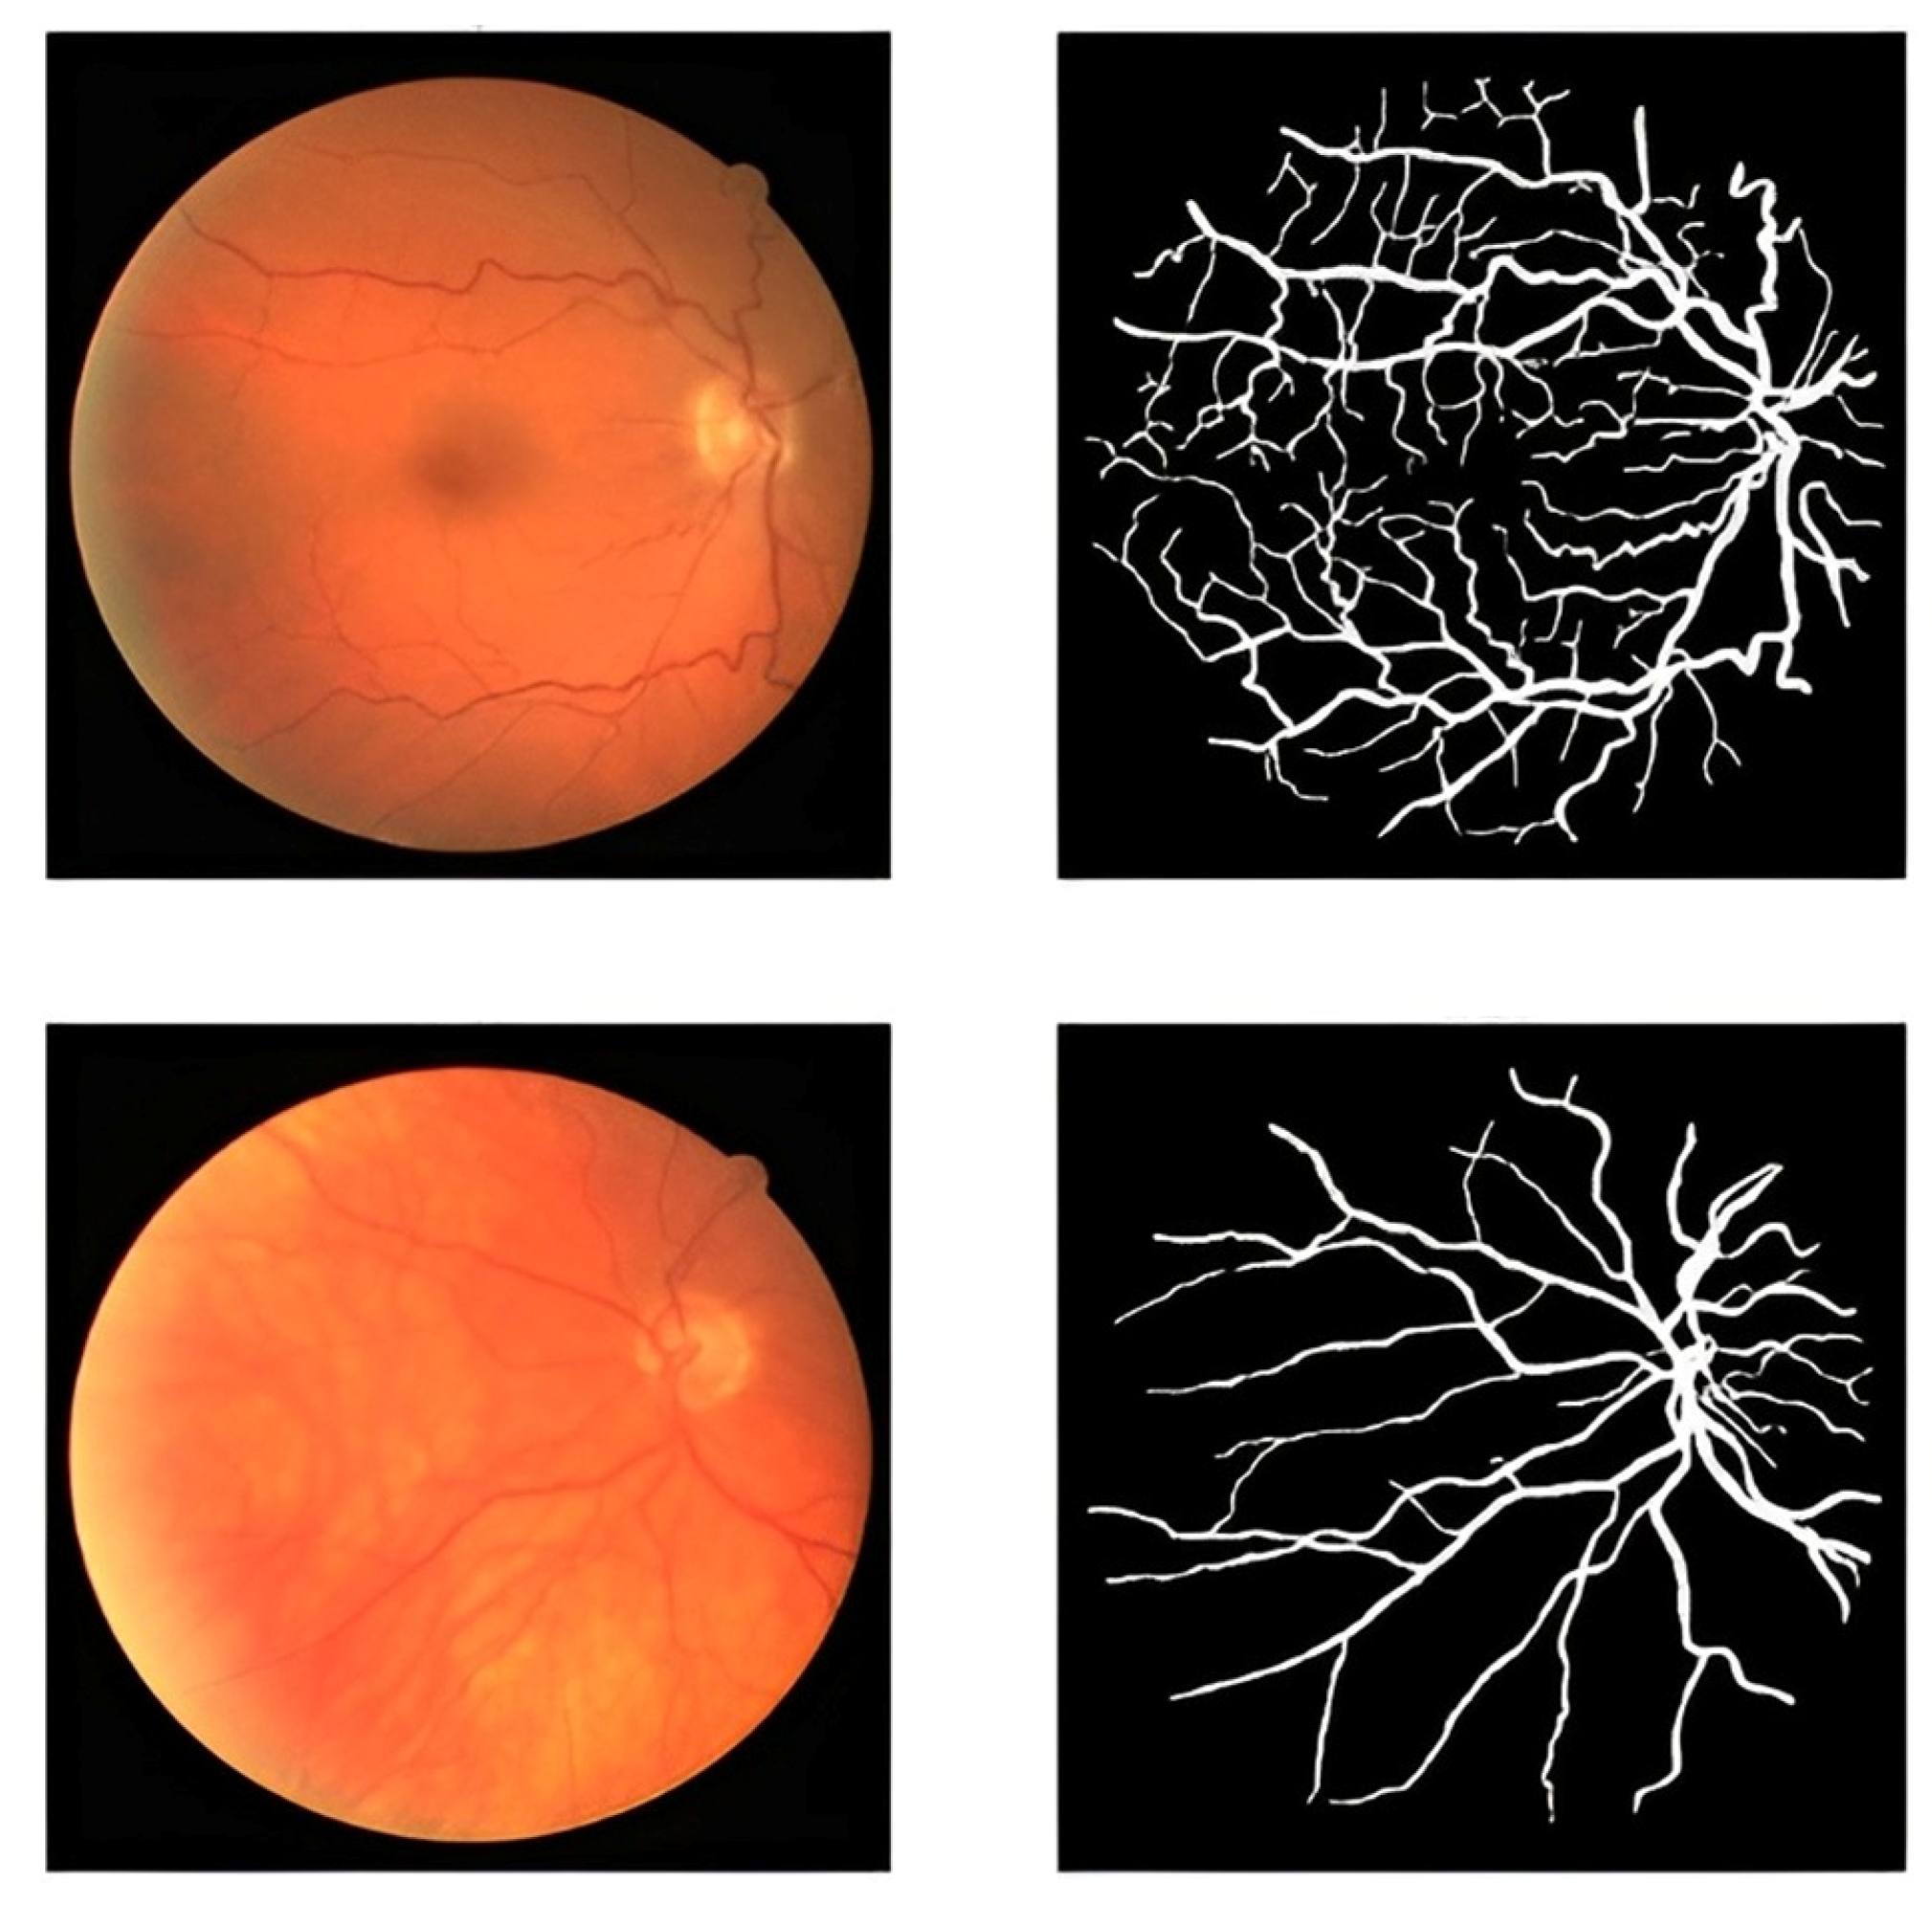

3.1. DRIVE Dataset

4.3. Results of Data Augmentation Layer

4.4. Results of Segmentation Stage